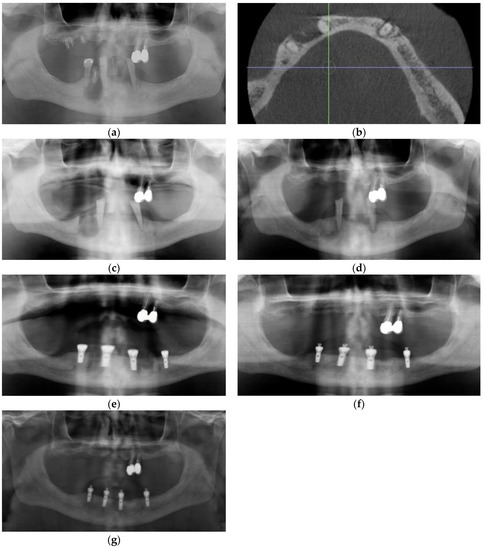

3.4. Case 4